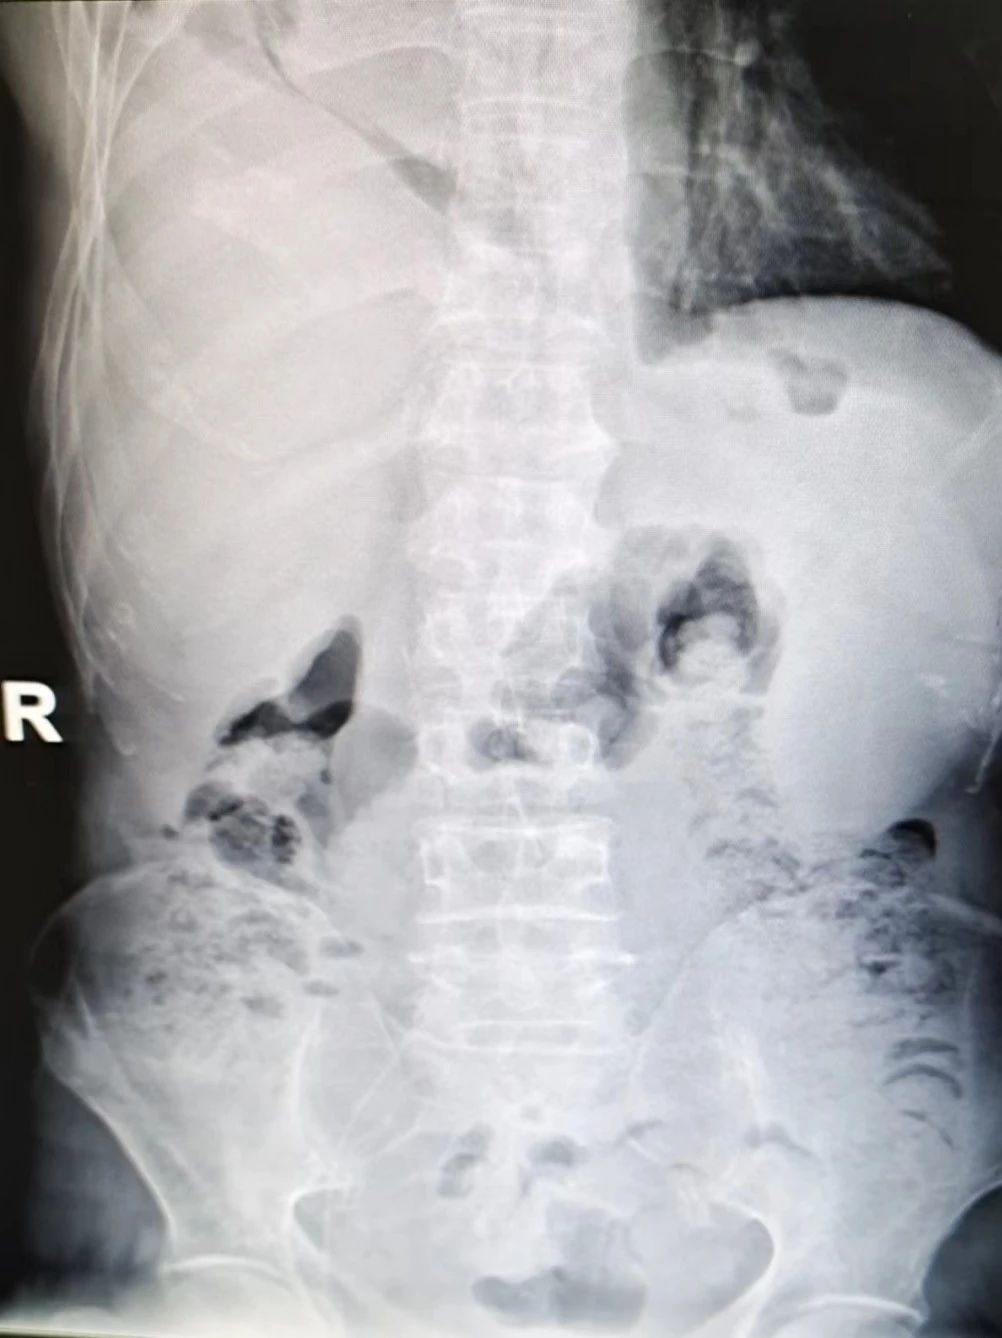

在取得患者家属知情同意后,我院血管通路专科护士在B超引导下成功为患者实施了股静脉PICC置管术,穿刺过程顺利,经X线确定PICC导管尖端已到达下腔静脉。

2.PICC导管由右侧大腿中上段入路股静脉穿刺置管,避开腹股沟皮肤皱褶处及关节活动部位,提高了患者舒适度,且易于固定与维护;

4.导管尖端准确置于下腔静脉,为患者建立了一条有效的静脉通路,使用寿命长达一年,并可满足患者化疗、肠外营养及支持用药治疗,也避免了化疗药物外渗引起的血管破坏。